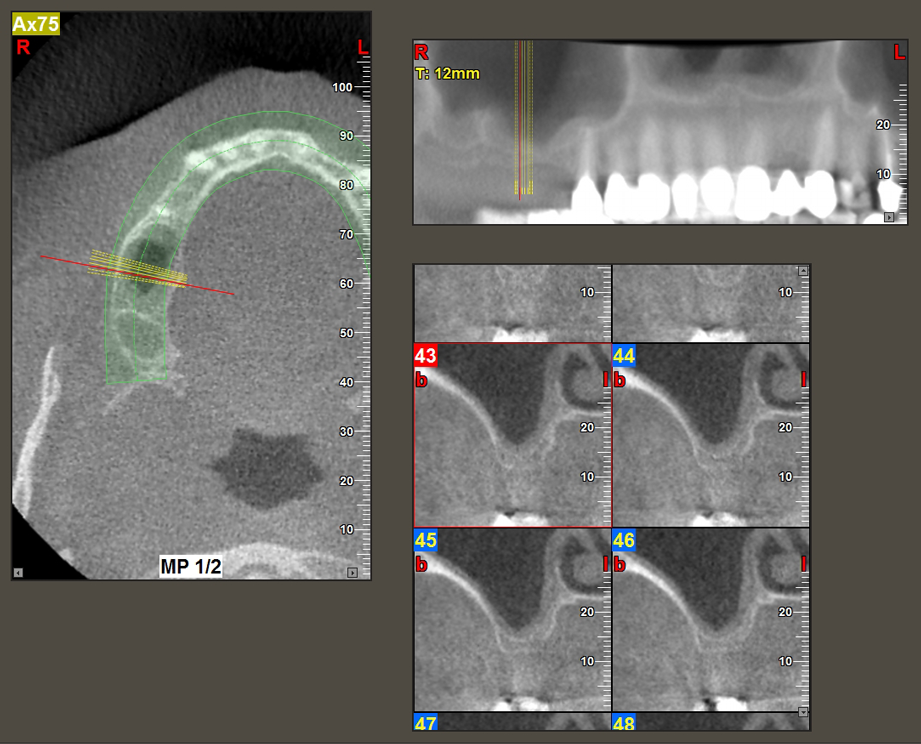

A 49-year-old female patient, a non-smoker and with nothing remarkable in her general medical history, was referred to our oral surgery practice for surgical extraction of tooth 16 and subsequent implantation. After the extraction, the patient experienced mild sinusitis trouble with the resultthat we initially waited six months before carrying out the measure. The residual bone height at the planned implant position measured 3-4 mm (Fig. 1 and 2).

Following an intermediate check (Fig. 4) a further preparation step was performed (Fig. 5). Afterwards, the hydraulic Z35P instrument was used to lift the membrane to the desired position (Fig. 6 and 7). This was followed by further piezosurgical preparation of the implant bed, concluded with a rotary bur and shoulder milling cutter up to the implant diameter of 4.8 mm. Before the implant was inserted, the augmentation material (particle size approx. 0.8-1.6 mm) was introduced underneath the Schneiderian membrane (Fig. 8).

Implantation and prosthetic restoration

To move the augmentation material in the direction of the maxillary sinus atraumatically, the implant was inserted very slowly by hand (Fig. 9). In the process, the membrane was pushed in the cranial direction once again. After two months, the surgical site healed without irritation. Six months later, the x-ray check showed a significant increase in opacity as an indication of ossification (Fig. 10). The prosthetic restoration was carried out with a metal-ceramic crown.